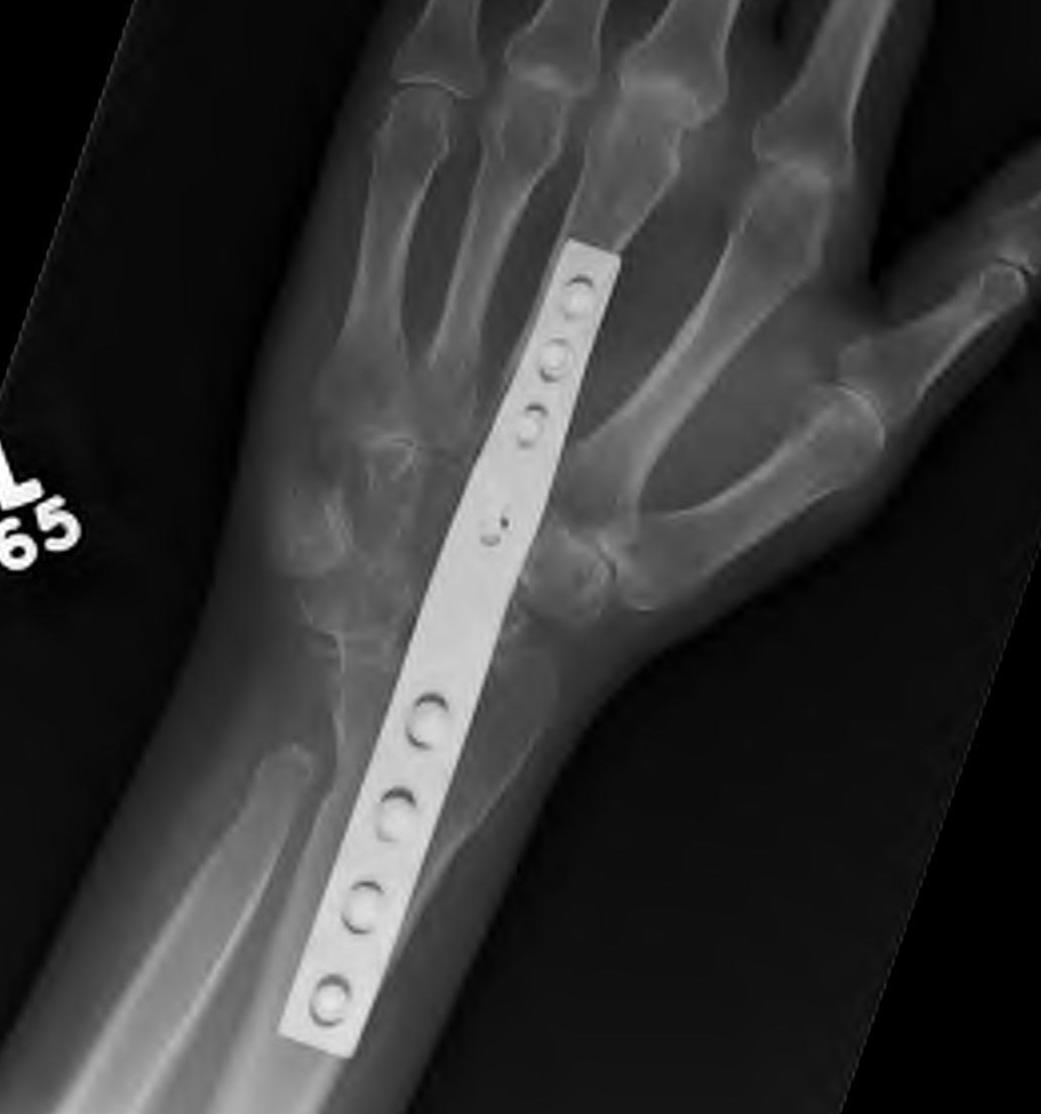

Total wrist arthrodesis

wrist fusionwrist fusion

Indications

Diffuse advance radiocarpal and mid carpal OA

Poor bone stock

Stiff wrist

Loss of wrist extensors

High demand

Technique

Wrist Fusion APWrist Fusion Lateral